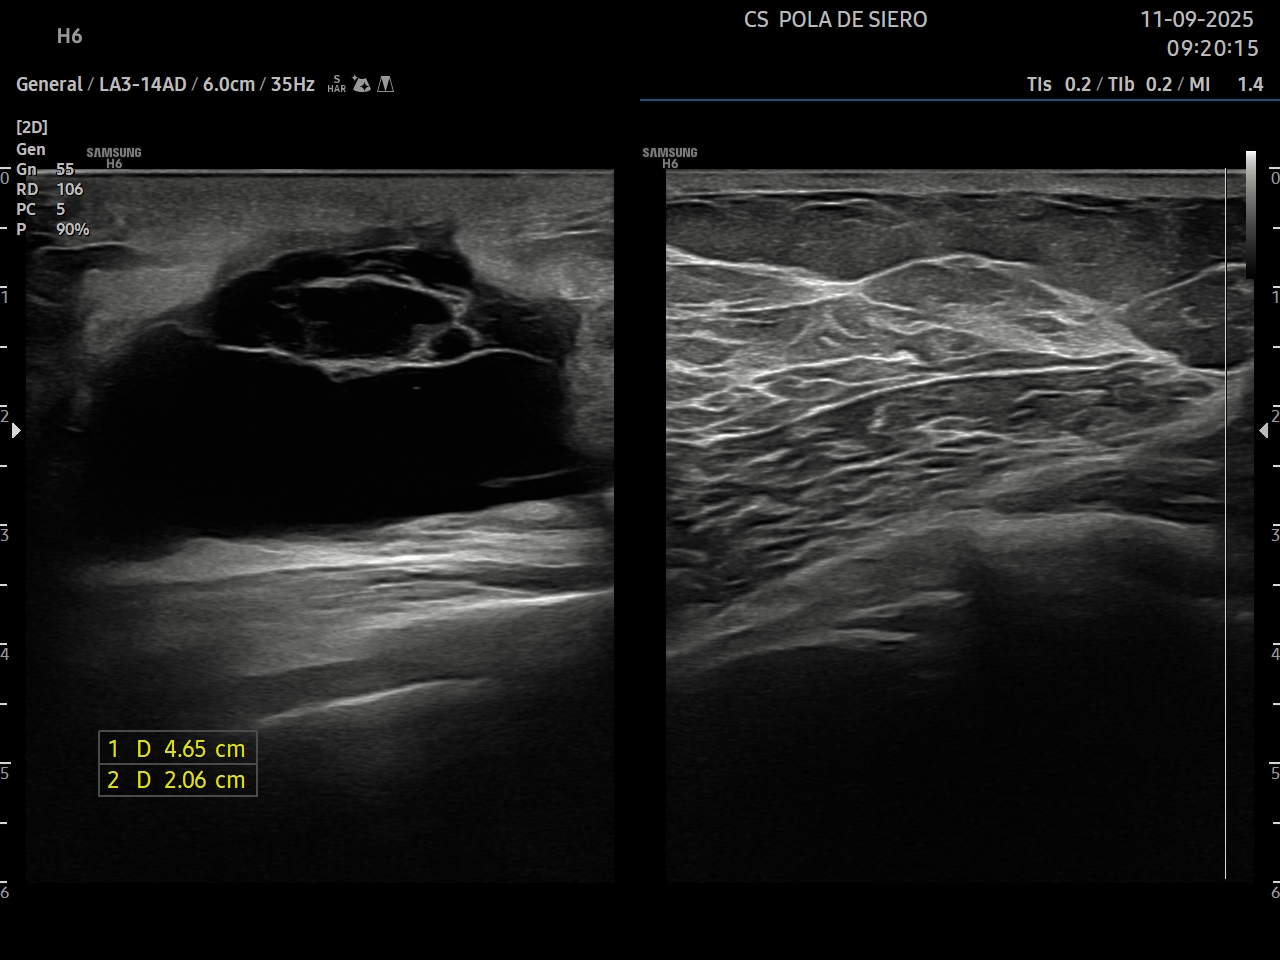

Ante la sospecha de infección local se realiza ecografía clínica para realizar diagnóstico diferencial entre celulitis y absceso de cara a un adecuado manejo del paciente.

Hallazgos ecográficos

Se identifica en el tejido celular subcutáneo una colección líquida, mal definida, de contornos irregulares, predominantemente hipoecoica con áreas ecogénicas en su interior. La lesión muestra refuerzo acústico posterior como corresponde a los contenidos líquidos. Con Doppler color presenta aumento de flujo periférico con escasa vascularización en su interior.

El diagnóstico diferencial se realizó entre celulitis y absceso. En este caso, fue diagnosticado de absceso en zona de la herida quirúrgica.